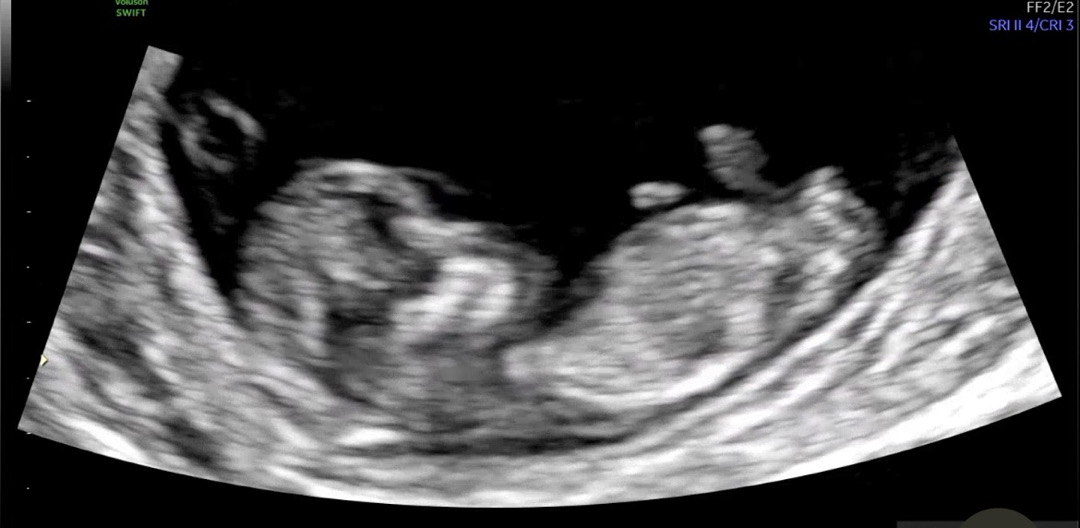

12주 각도법으로 성별 유추해주세요!

마구마구 예측 부탁드립니당❤️